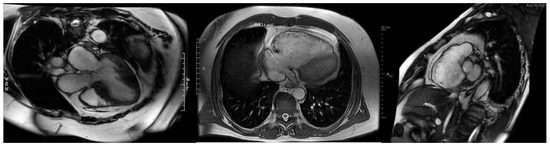

2.2. Cardiac Magnetic Resonance Imaging: Gold Standard